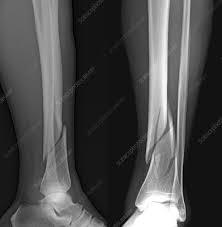

simple fracture

bone breaks but doesn't pierce the skin

compound fracture

bone breaks and pierces the skin

comminuted fracture

bone shatters into small pieces

spiral fracture

caused by twisting; break at an angle

stress fracture

caused by overuse injury; tiny fracture lines